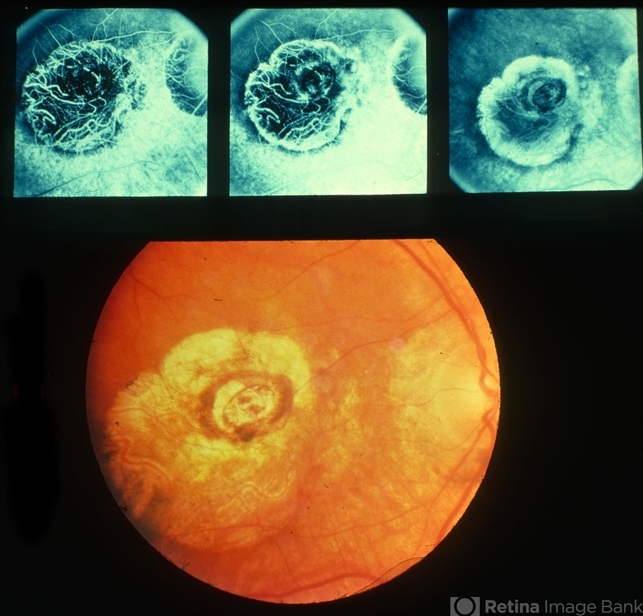

- macular staphyloma

- Macular staphyloma with FA.